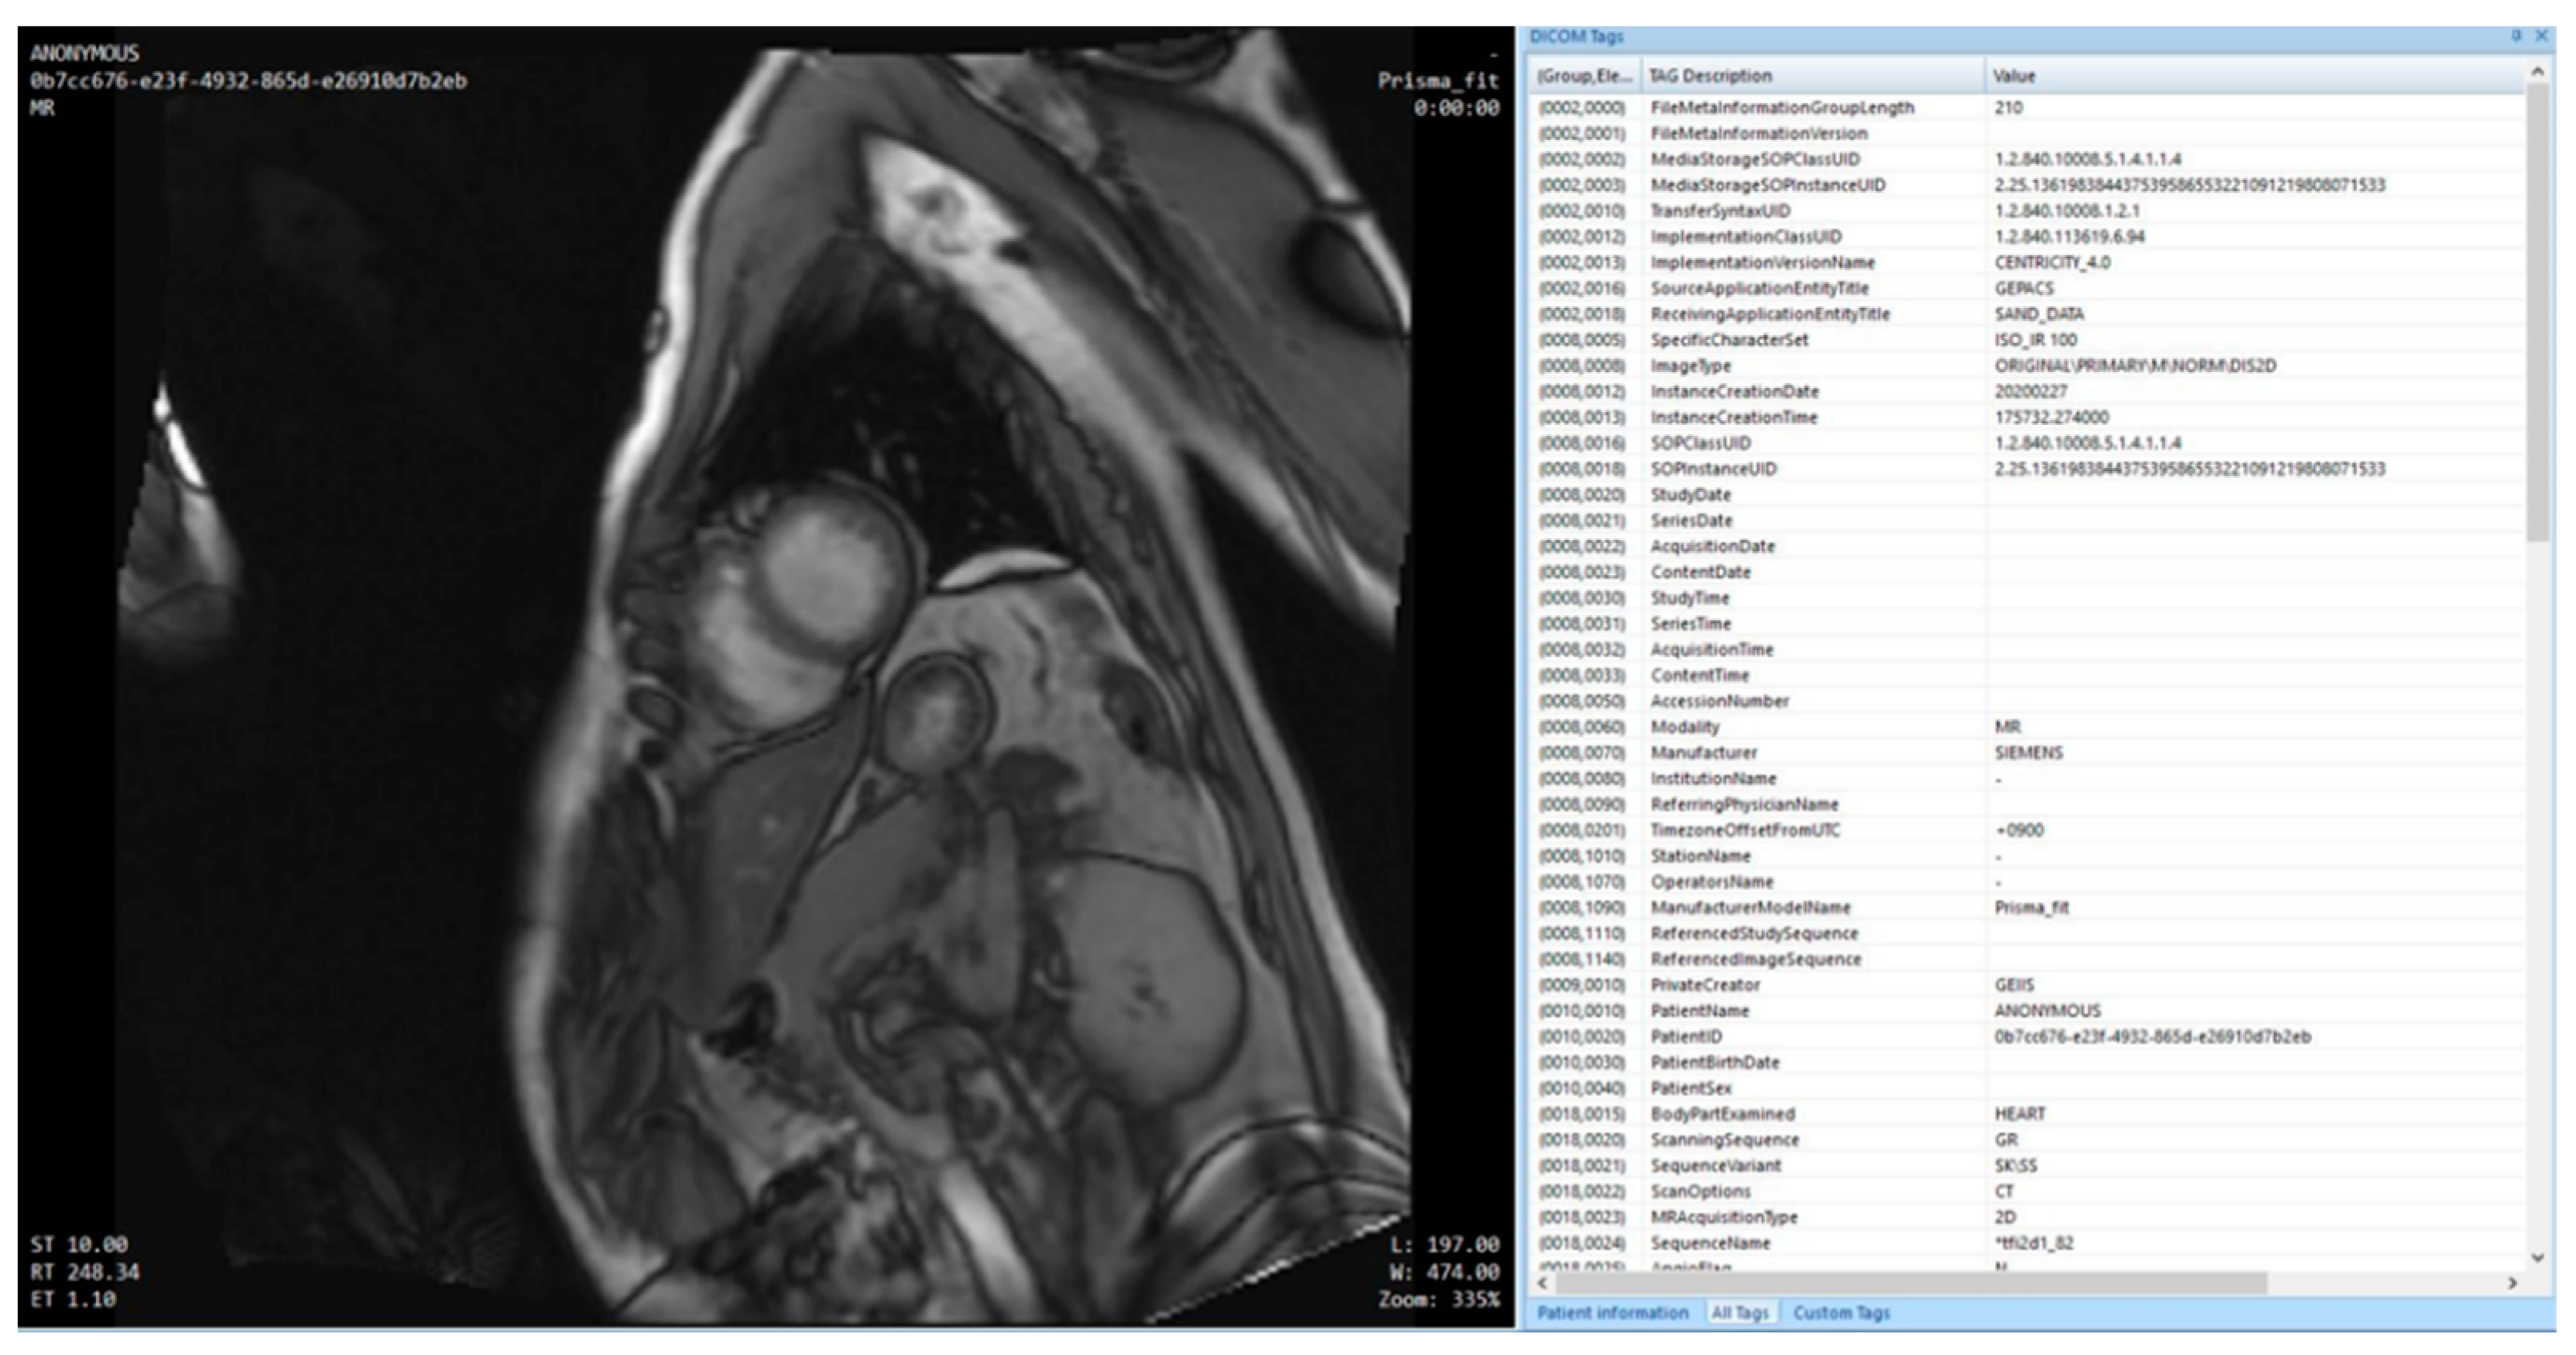

When comparing MRI data using the CTP from the original to the data after the de-identifier process, data that are at risk of personal information leaks are either removed or de-identified.

In Figure 10, data that needs to be protected for personal information related issues is redacted in the cardiovascular MRI original image. Redacted information are items related to DICOM de-identifier methods and basic profile and include the patient’s name, MR imaging location, name of the specialist, and date of imaging, among others. Information processes by de-identifier processes are shown in Figure 11.

In Figure 11, data elements that were shown in the original are nonexistent or changed to different value. The risk of personal information leaks are minimized and only information needed for research is retained.